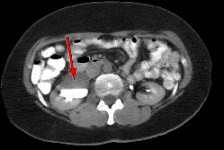

Fig.1 Fig.2 Fig.3

FINDINGS: The ultrasound (not shown) demonstrated dilated collecting system versus extrarenal pelvis on the right. Fig. 1 and Fig. 2 are nephrographic and delayed images through the kidneys. They demonstrate a large dilated right renal pelvis (red arrows) with urine-contrast level and a normal-sized ureter consistent with UPJ obstruction. Fig. 3 is a 3D image from a renal MRA showing an accessory right renal artery (yellow arrows) supplying the right lower pole and impressing upon the right UPJ, explaining the UPJ obstruction. Normal renal arteries are also clearly seen (green arrows)